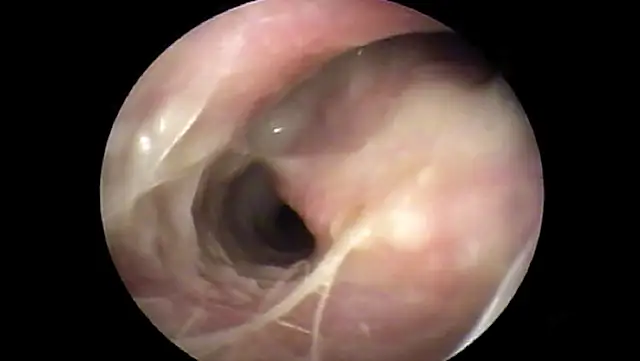

In some dogs, the pars flaccida of the eardrum may be bulging from fluid pressure in the middle ear behind it (Figure 16) and may obscure visualization of the pars tensa. Some have suggested that this enlargement may be caused by degranulation of mast cells and resultant edema from atopic dermatitis.7,8 This condition is frequently mistaken for a mass in the external canal and should be closely evaluated.

Otoscopic image of domed eardrum with hair and yellow exudate visible in internal ear canal.

FIGURE 16

Bulging eardrum caused by increased fluid pressure in the middle ear

In the Cavalier King Charles spaniel, a condition called primary secretory otitis media can cause bulging of the eardrum resulting from the failure of mucoid drainage from the tympanic bulla through the auditory tube.